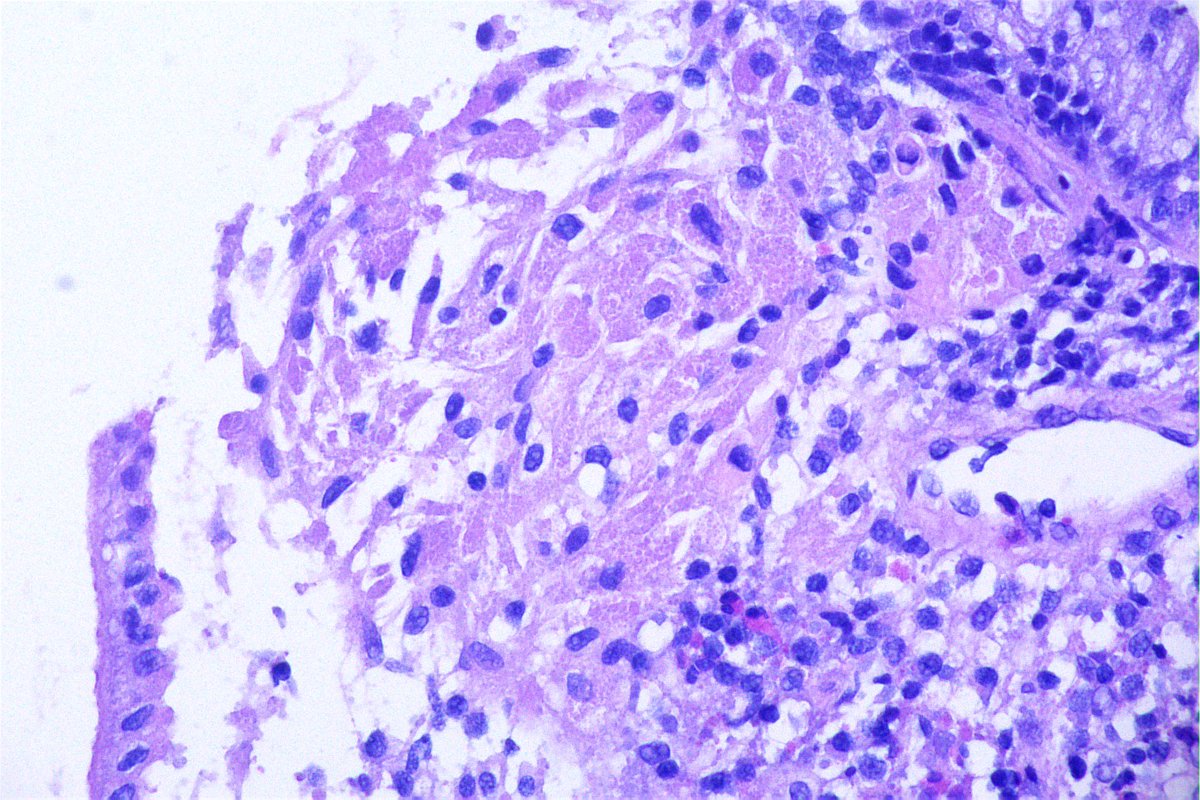

@GeronimoJrLapac

Ger么nimo Jr.

2 months

F, 47yo. The clinical information is: subepithelial lesion in the ileocecal valve. #gipath